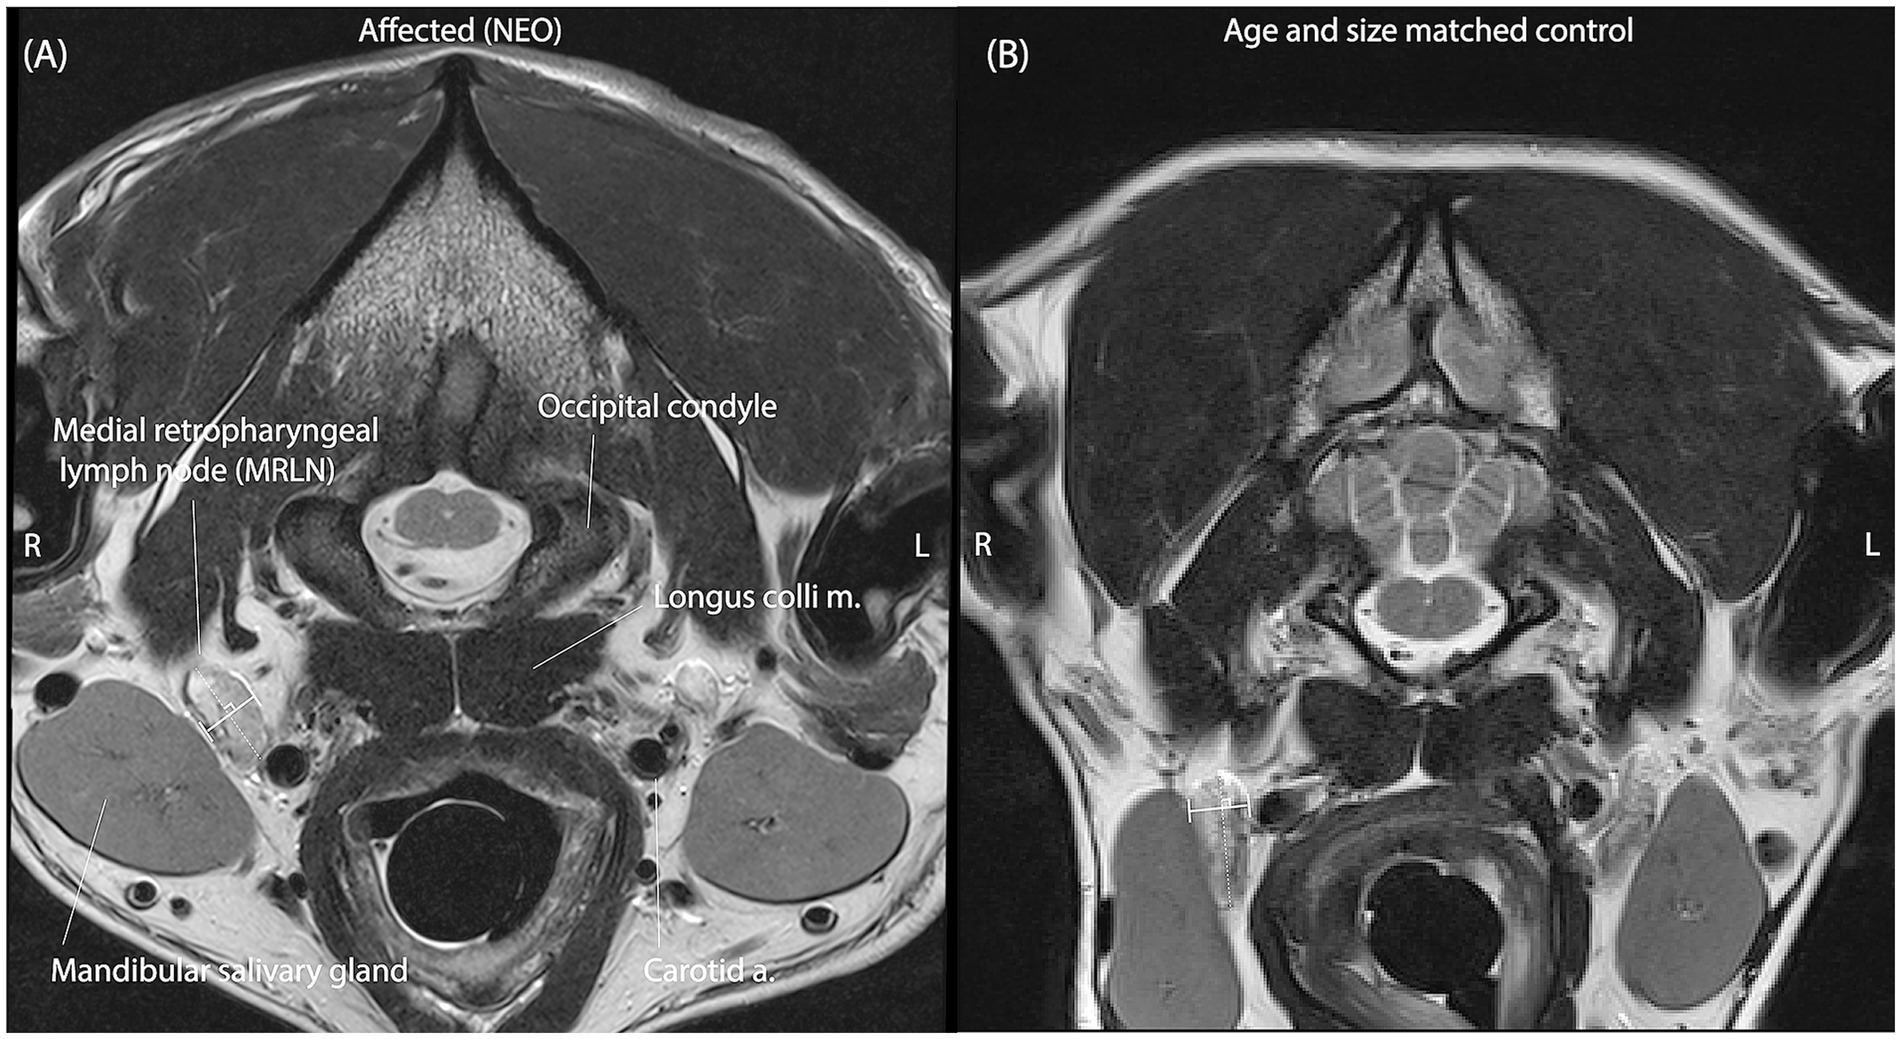

MRLNs were identified by their location medial to the mandibular salivary gland and lateral to the common carotid artery near the level of the atlanto-occipital joint (Figure 2) (6). Two observers blinded to all clinical information viewed only the T2 transverse spin-echo series and identified slices representing the maximum short-axis transverse diameter (M_SATD) of the left and right MRLNs independently. In cases where more than one MRLN was identified on a side, only the larger one was recorded. For both the left and right sides, each observer used a caliper to estimate the M_SATD in millimeters (7).

Figure 2. Representative T2 spin-echo slices are selected by both observers independently to represent the M_SATD of the right medial retropharyngeal lymph node in two different dogs. (A) A dog with intracranial neoplasia (affected subgroup NEO). (B) A dog of similar size and age from the control group. Anatomical landmarks for identification of the MRLN are labeled in panel A. In each panel, the solid white line between perpendicular shorter white lines illustrates the selected short-axis transverse diameter of the lymph node for the represented slice.